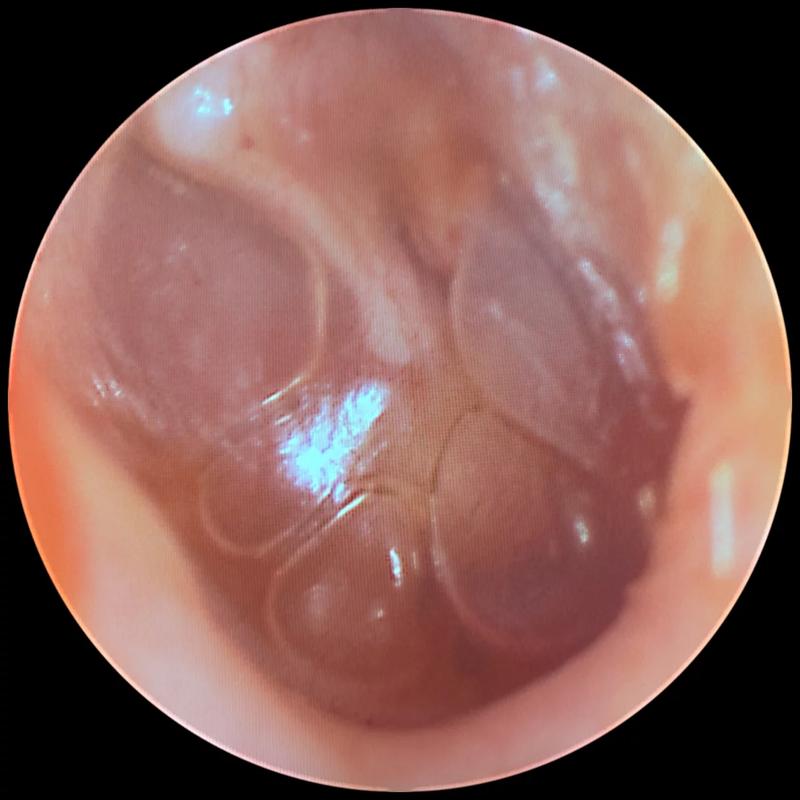

Objawy zapalenia ucha mogą przybierać różne formy, ale najczęściej obserwujemy silny ból, gorączkę oraz ogólne rozdrażnienie. Dzieci, które jeszcze nie potrafią wyrażać swoich myśli słowami, sygnalizują dolegliwości poprzez płacz, pocieranie ucha czy trudności z karmieniem. Zwłaszcza gdy nacisk na ucho przynosi im nieprzyjemne doznania. Czasami maluchy doświadczają również wycieków z ucha. Cóż, maluchy muszą jakoś komunikować swoje potrzeby, a łzy i brudne ubrania znajdują się wśród najczęstszych sposobów! Właściwie złapanie zapalenia ucha przypomina łapanie złotej rybki – każdy rodzic stara się tego unikać, ale kiedy już to się zdarzy, staje przed dylematem: co teraz zrobić?

Zapalenie ucha – rodzaje i dlaczego nie jest zaraźliwe

Wyróżniamy trzy rodzaje zapalenia ucha: zewnętrzne, środkowe i wewnętrzne. To ostatnie wydarza się niezwykle rzadko, natomiast zapalenie ucha środkowego występuje dość często, szczególnie u dzieci. Dlaczego tak się dzieje? Otóż ich trąbki Eustachiusza, czyli te fajne rurki łączące ucho z nosogardłem, są u maluchów krótsze i bardziej poziome. Właśnie dlatego wirusy z kataru mogą z łatwością przedostać się do ucha, co prowadzi do problemów. Pragnę jednak przypomnieć – zapalenie ucha nie przenosi się jak grypa; to wirusy i bakterie mogą być przekazywane. Dlatego dbajmy o zasady higieny, ponieważ to klucz do zdrowia.